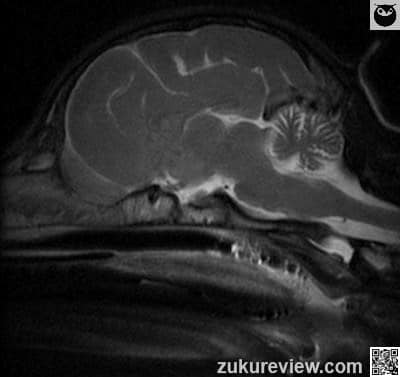

MRI interpretation: Representative T1 and T2 weighted MRI images. The cerebellum is small with a resulting large collection of CSF in the vicinity. There are no other abnormalities of signal intensity. Follow this link and click additional images to see another example of cerebellar hypoplasia in a dog.

Radiographic interpretation and images courtesy, Dr A. Zwingenberger and Veterinary Radiology.